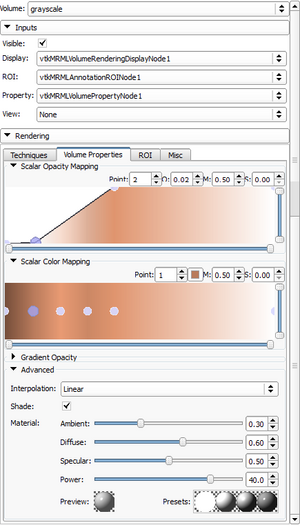

| qMRMLModelDisplayNodeWidget |

|

A widget that represents any vtkMRMLModelDisplayNode |

| qMRMLDisplayNodeWidget |

|

A widget that represents any vtkMRMLDisplayNode |

| qMRMLModelInfoWidget |

|

A widget that shows model internal data properties |

| qMRMLVolumeInfoWidget |

|

A widget that shows volume internal data properties |